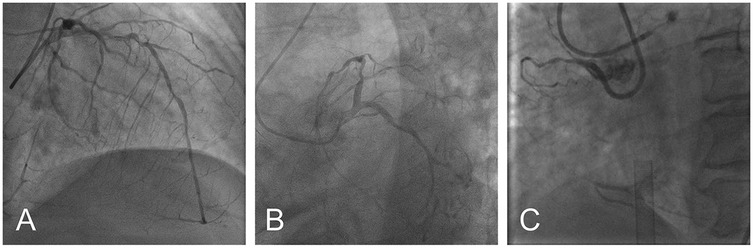

Based on these findings, the patient was diagnosed with severe AS, acute myocardial infarction, Killip III, and acute heart failure. Subsequently, the patient was provided with non-invasive positive pressure ventilation and pharmacologic treatment to correct heart function, significantly relieving her dyspnea. Coronary angiography (CAG) revealed 90% stenosis with calcification in the proximal left anterior descending artery (LAD), 70%–80% stenosis in the mid-segment, with thrombolysis in myocardial infarction (TIMI) flow grade 3, and retrograde perfusion to the right coronary artery (RCA) via the LAD (Figure 2A). The proximal left circumflex artery indicated 50%–60% stenosis, with TIMI flow grade 3 (Figure 2B), and RCA was completely occluded (Figure 2C). During CAG, the patient developed acute left heart failure and was promptly transferred to the coronary care unit (CCU) for further management of heart failure. A multidisciplinary consultation was held to discuss whether to proceed with open-heart surgery or interventional treatment and the choice of anesthetic approach. Given the patient's critical condition, with severe AS, complex CAD, and low ejection fraction, the risks of surgical aortic valve replacement (SAVR) and coronary artery bypass grafting (CABG) were considered extremely high. Our center has extensive clinical experience with ECMO-assisted TAVR in treating severe heart failure. Considering the patient's specific condition, the team determined that a combination of ECMO-assisted PCI and TAVR would be the safest approach for treatment. To reduce the risk of cardiac arrest, the treatment plan involved initial ECMO insertion under light sedation, followed by endotracheal intubation. After thoroughly informing the patient's family about the risks and treatment plan, the family signed the informed consent form. On the 10th day of hospitalization, the patient underwent the procedure in the interventional operating room.

Figure 2

Preoperative coronary angiography: severe ostial stenosis of LAD (A) severe proximal stenosis of LCX (B) total occlusion of RCA (C) (LAD, left anterior descending artery; LCX, left circumflex artery; RCA, right coronary artery).